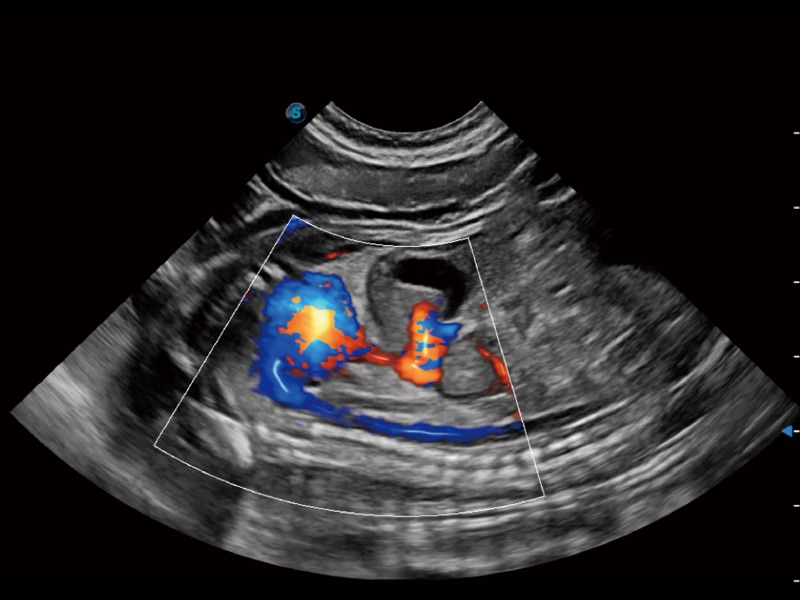

通过创新的 Matrix E自适应滤波器和超长时间域算法,极大提升超低速微细血流的检出能力,同时更精准地滤除软组织和噪声信号,为兽用医生提供以往无法通过常规血流获得的疾病诊断信息。

通过色彩血流和实时宽景相结合,可观察到完整的静脉或动脉的血流,方便医生检查。实时扫查过程中,如有任何操作失误也可以很容易地进行回扫擦除,而不会中断扫查。

一键自动识别膀胱壁及自动测量膀胱容积,不受膀胱形状和大小的限制,帮助医生快速精准获得测量的数据。